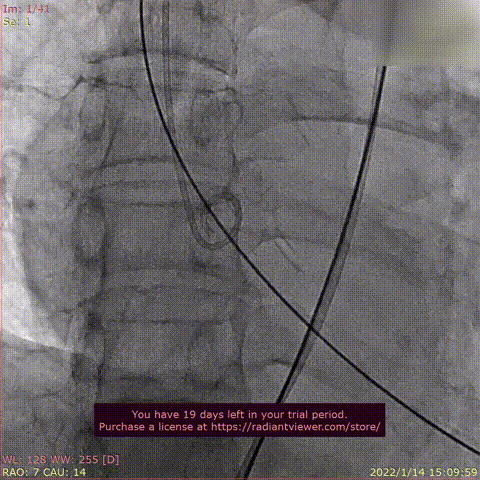

Case 5

患者为68岁男性,因“活动后心累,气紧半年,加重1周“主诉入院。术前超声提示全心增大,左室肥厚,LVDD 75mm ,LVEF 48%,主动脉瓣重度反流。术后即刻主动脉瓣大量反流消失,LVDD 59mm,左室较术前显著缩小。

术前DSA造影